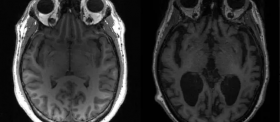

Donanemabe – Tratamento Para Declínio Cognitivo

O donanemabe, fabricado pela Eli Lilly, é o mais recente de uma nova classe de tratamentos que pode retardar o…